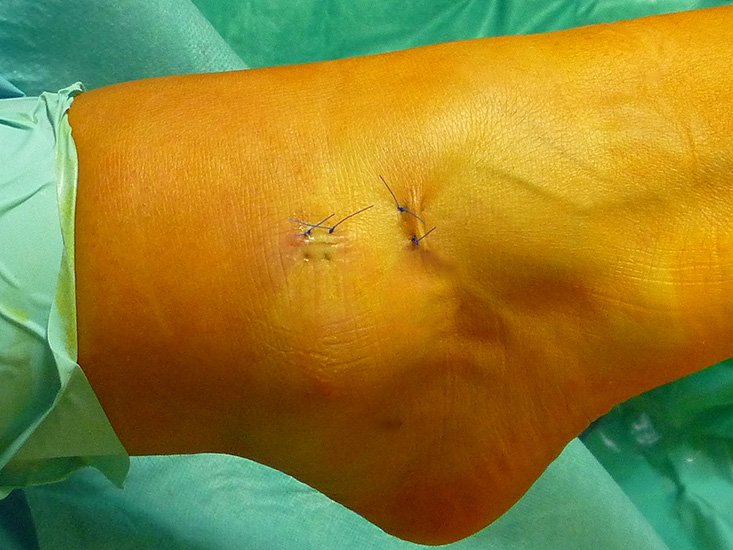

- Wundheilungsstörungen/Fistelbildung: das Risiko einer Wundheilungsstörung oder Fistelbildung kann durch einen suffizienten Wundverschluss deutlich reduziert werden. Die Portale sollten anstelle von Klammerpflastern o. ä. mittels Einzelknopf- oder Einzelknopfrückstichnähte verschlossen werden. Die Autorin empfiehlt 2 Nähte pro Portal, um die Haut fest zu adaptieren. Eine Teilbelastung des Fußes sollte mindestens eingehalten werden, bis die Wundsekretion sistiert.